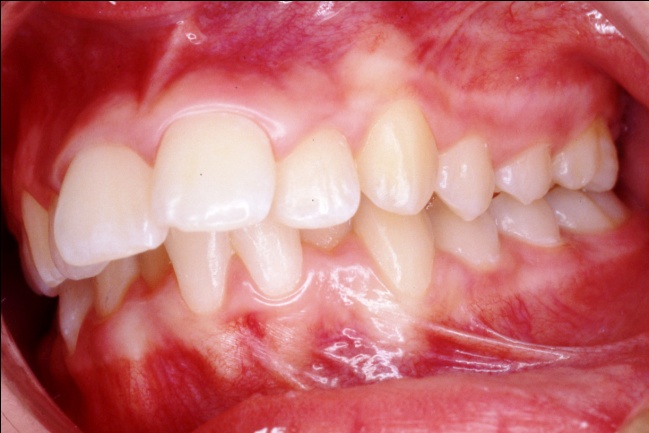

4 - Quand les extractions embellissent… ou enlaidissent

Le changement est spectaculaire : le sourire et le profil sont métamorphosés, avec un effet attendu sur le développement psychologique de l’enfant. Ici, les extractions étaient pleinement justifiées par un profil initial très biprotrusif, permettant une nette amélioration esthétique. Mais appliquée à un profil normal, la même mécanique pourrait avoir l’effet inverse : lèvres rétractées, ourlet naturel perdu et angle nasolabial ouvert, donnant une proéminence excessive au nez.